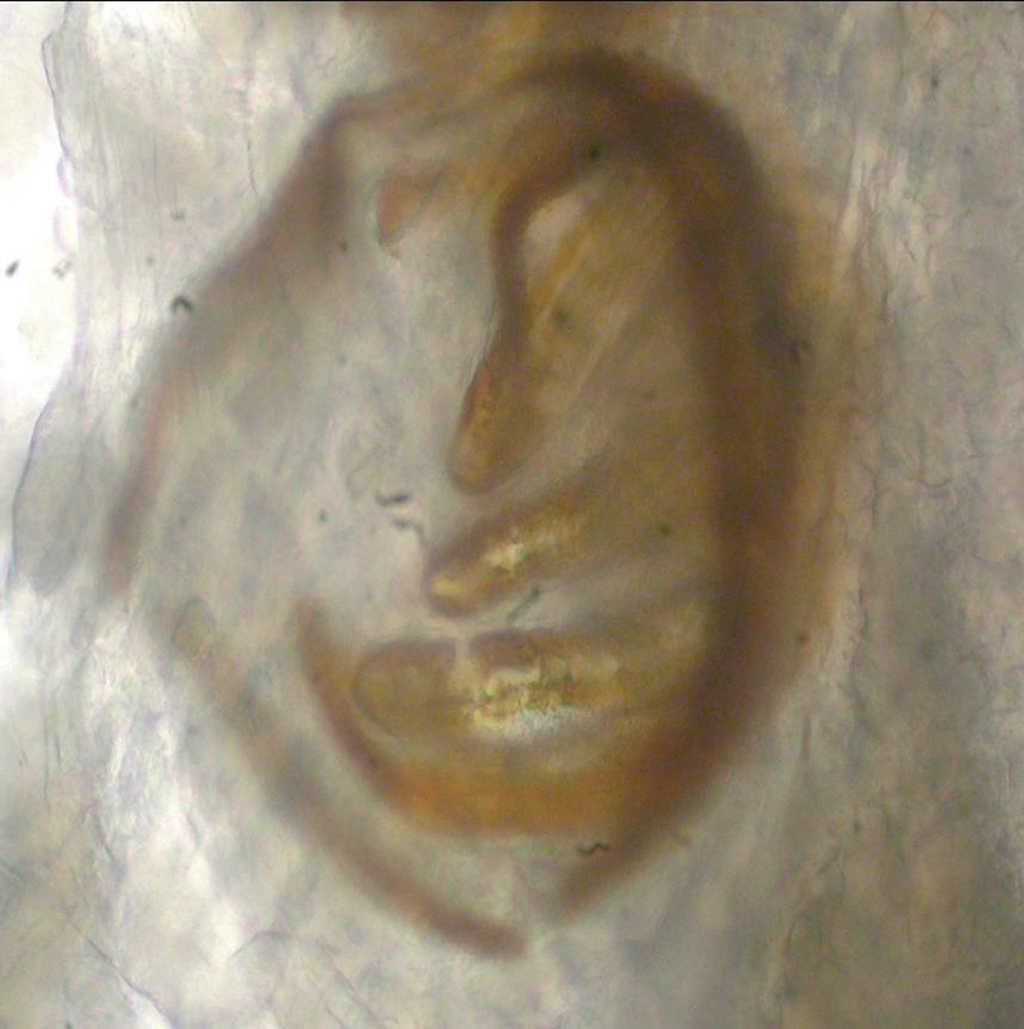

Fig. 2.--Larva móvil.

A la exploración, se objetivaba una gran masa tumoral en la cara anterior del cuello, con múltiples zonas ulceradas, nodulares, papilomatosas y criptas (fig. 1). De la profundidad de estas zonas necróticas se extrajo una larva móvil (fig. 2).